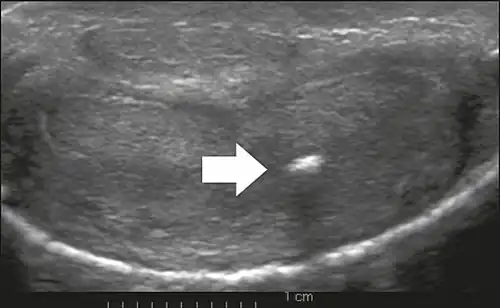

On penile ultrasonography, the typical appearance is hyperechoic focal thickening of the tunica albuginea. Due to associated calcifications, the imaging of patients with Peyronie's disease shows acoustic shadowing, as illustrated in figures below. Less common findings, attributed to earlier stages of the disease (still mild fibrosis), are hypoechoic lesions with focal thickening of the paracavernous tissues, echoic focal thickening of the tunica without posterior acoustic shadowing, retractile isoechoic lesions with posterior attenuation of the beam, and focal loss of the continuity of the tunica albuginea.

Transverse ultrasound of the penis, in a ventral view, in the middle portion of the penis. Note the echoic image with posterior acoustic shadowing, corresponding to calcification (arrow), in the left corpus cavernosum.[14]